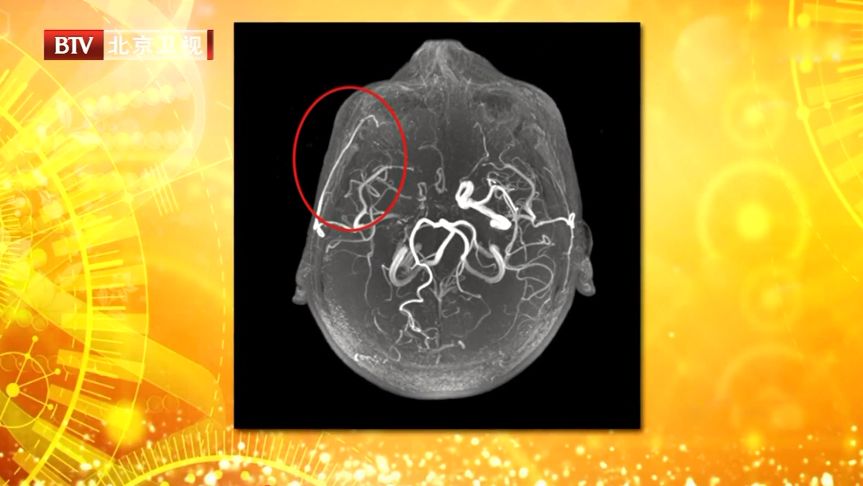

2、 梗塞后长侧支循环,一侧太阳穴以及脑后痛

大脑主干血管堵塞时,身体会努力建立侧支循环,以补充主干血循环不足的情况,但在侧支循环生长时,血管扩张可能会引发头痛。

这种头痛通常出现在一侧太阳穴以及脑后,特点是随着心跳的节奏跳痛。